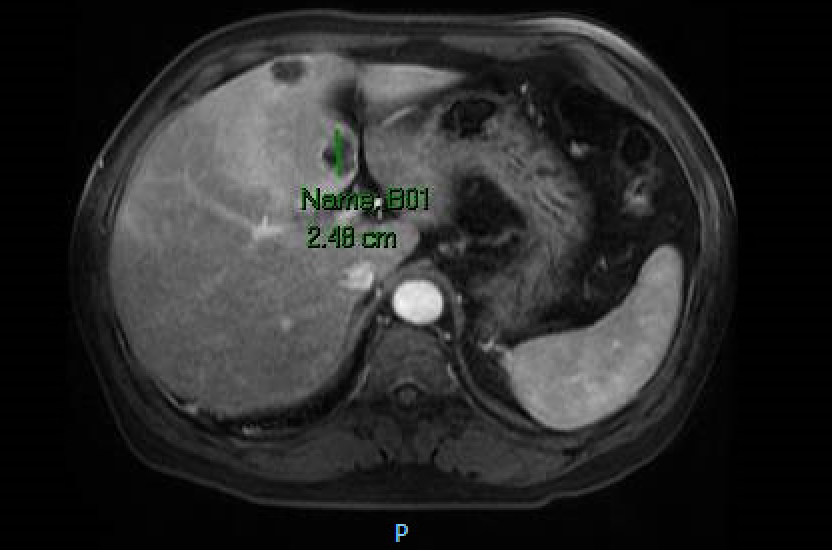

Case Presentation: A 55 year-old Korean male with a past medical history of hypertension and hyperlipidemia presented to the Emergency Department after feeling short of breath with chest pain, palpitations, mottled skin and blue lips. He endorsed five days of fever, headache, shortness of breath, abdominal pain and nausea. He denied recent travel and sick contacts. He was febrile to 101.6ºF and on examination was diaphoretic, tachycardic to 139 bpm and tachypneic to 36 breaths/minute. Blood work showed transaminitis (AST 82 and ALT 139 u/L) along with elevations in alkaline phosphatase (139 u/L), lactate (2.6 mmol/L) and GGT (280 u/L). Initial EKG taken by EMS revealed a Brugada pattern (ST elevations in V1-V3 with right bundle branch block [RBBB]). He was admitted and treated for severe sepsis. Repeat EKG showed persistent RBBB with resolution of ST changes. Chest X-ray, respiratory viral panel and urinalysis were unremarkable. Cardiac enzymes were negative and echocardiogram revealed no valvular or wall motion abnormalities. A CT abdomen and pelvis was done given an unclear source of infection in the setting of transaminitis. It revealed multiple hypo-attenuating indeterminate liver lesions. MRI demonstrated liver lesions suspicious for abscesses along with partial middle hepatic vein thrombosis. Blood cultures grew Klebsiella Pneumoniae. The liver abscesses were too small to drain. A PICC line was placed for six weeks of ceftriaxone. For hepatic vein thrombosis treatment the patient was started on Xarelto. Electrophysiology (EP) was consulted and attributed the Brugada pattern to persistent high fever in the setting of severe sepsis. They felt that no intervention was warranted at that time and the patient was monitored on telemetry without any further EKG abnormalities. Two months later the patient was asymptomatic and repeat CT showed complete resolution of liver abscesses.